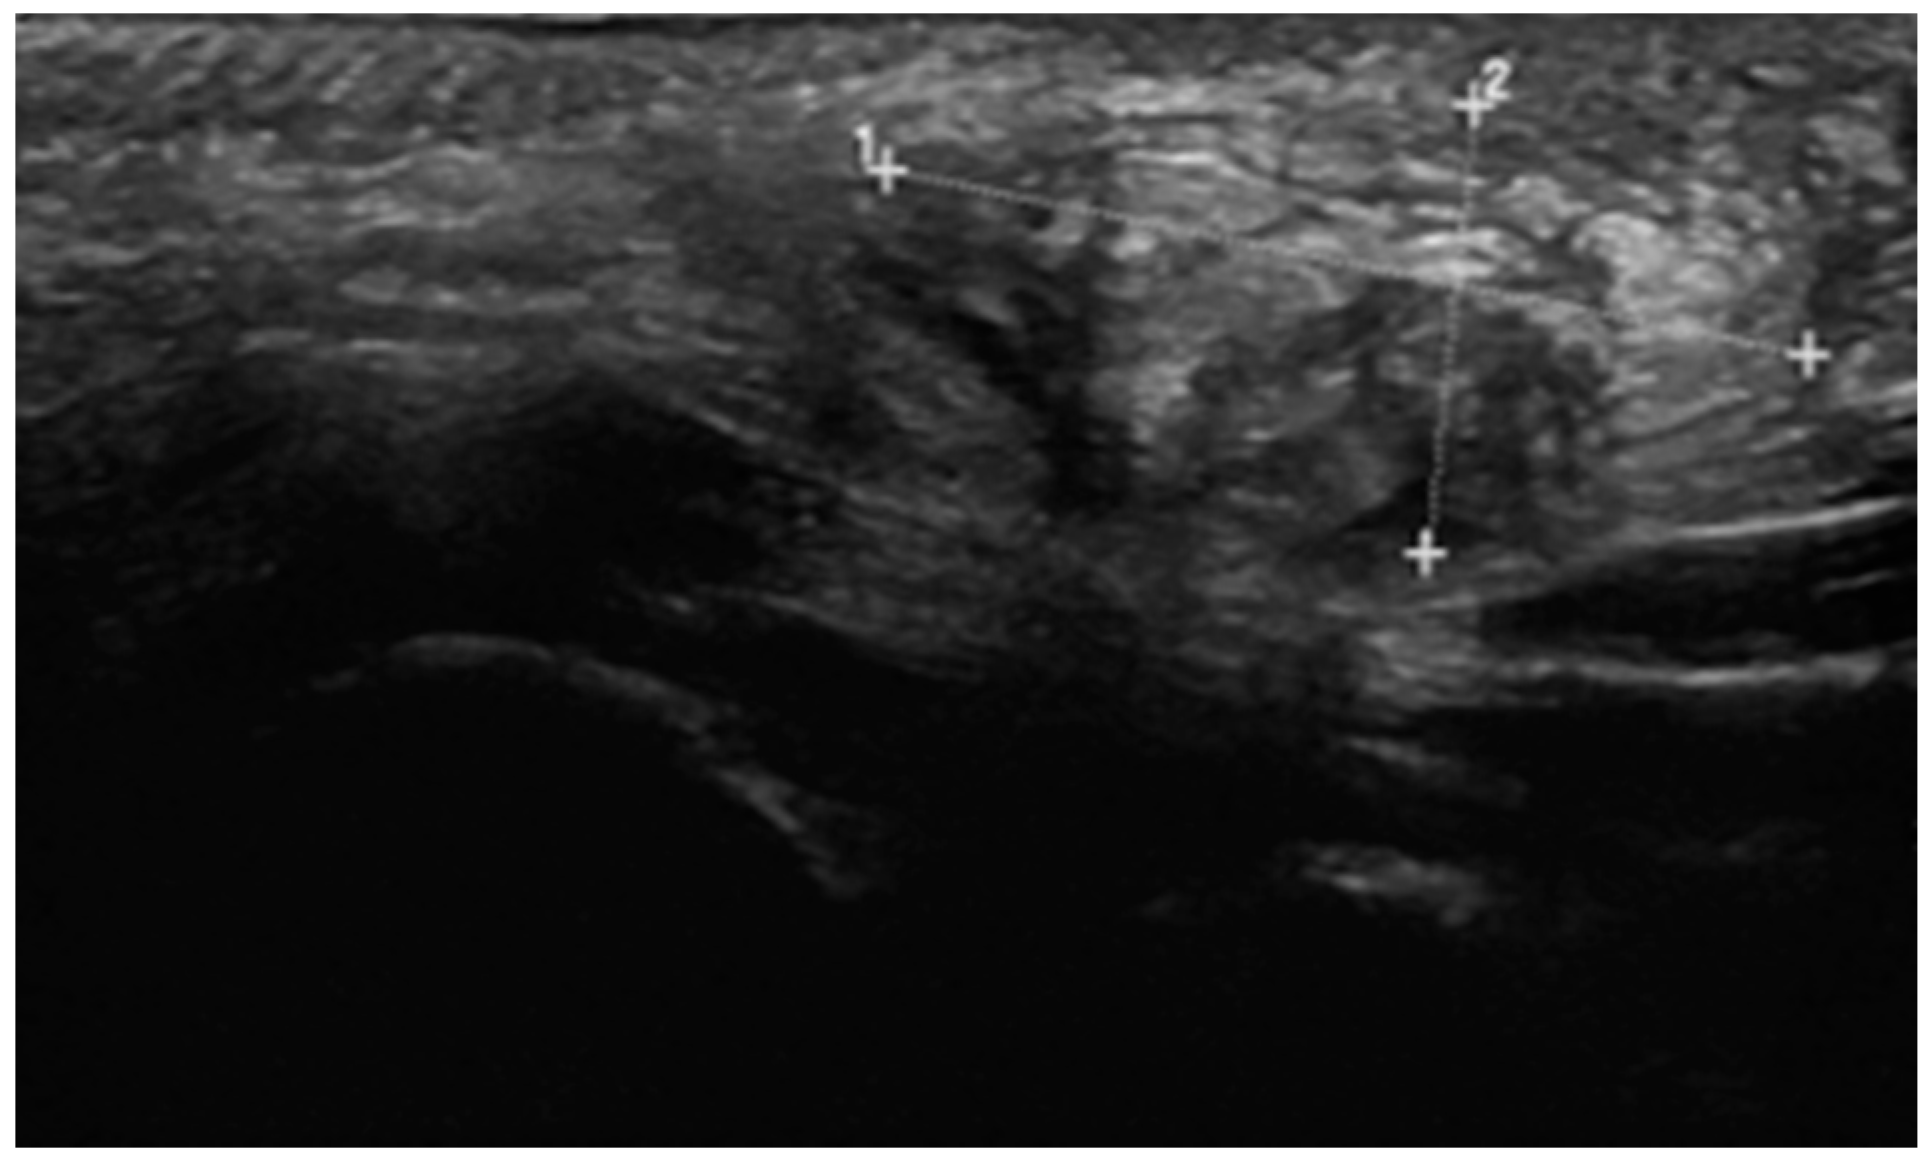

2.1. Case 1

2.2. Case 2